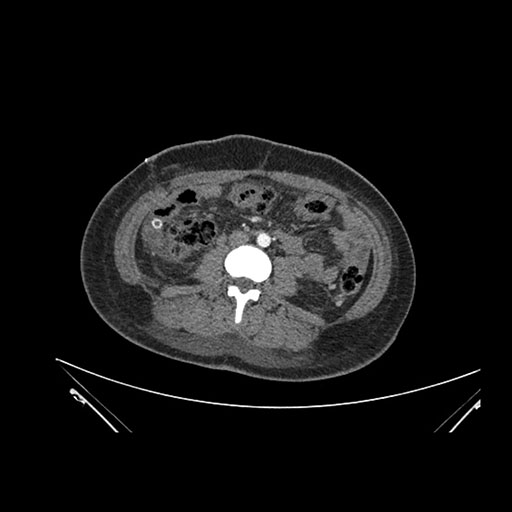

Axial Venous